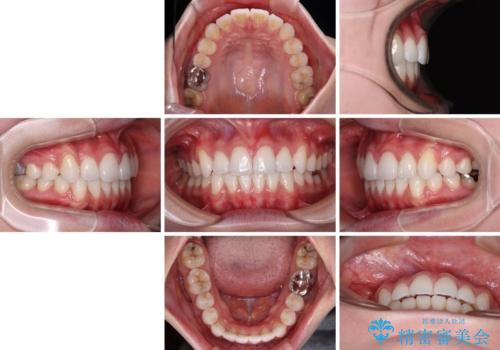

補助装置を使用したことで、口元が突出することもなく、スムーズに仕上げることができました。